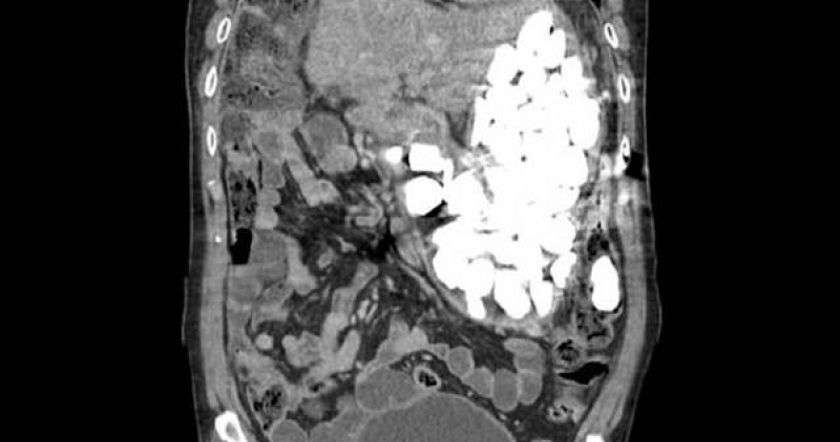

В ходе беседы с врачом пациент признался, что часто глотает камни и монеты, чтобы успокоиться. Рентген показал, что мужчина довольно нервный: весь желудок был заполнен камнями, монетами и бутылочными крышками.

Медикам пришлось проводить операцию для того, чтобы очистить желудок пациента. Общая масса извлеченных оттуда предметов составила около двух килограммов.